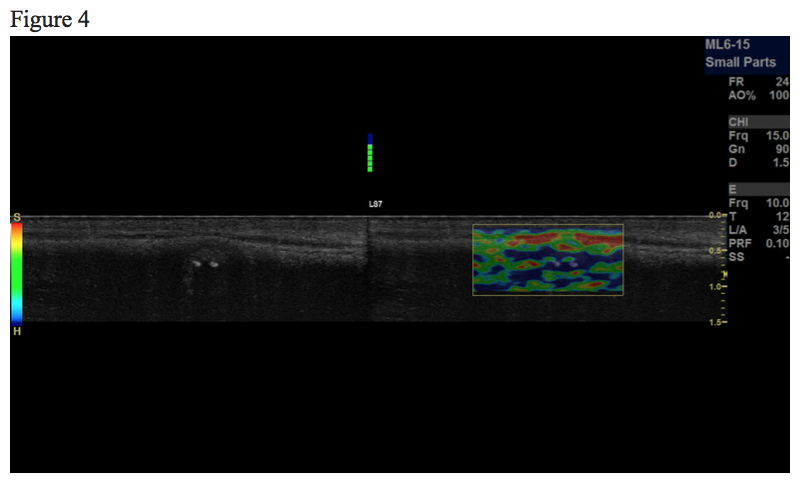

Figure 1, 2, 3 and 4 show the same hypoechoic lesion, a Peyronie’s plaque, in the penile connective tissue. The lesion has a well-defined circumference.

Figure 3. B-mode image. The lesion contains 2 circular hyperechoic dots, marked with red arrows, which represents calcification with acoustic shadowing, marked with blue arrows.